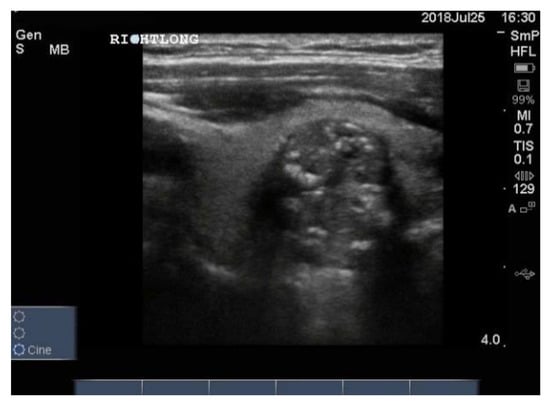

Three examples of papillary thyroid cancer are shown here. Firstly, a large typical papillary cancer with the characteristic microcalcifications is seen in Figure 11.

Figure 11.

Thyroid ultrasound from a patient with confirmed papillary thyroid cancer. The nodule is large (3 cm) and hypoechoic with an indistinct irregular edge and central microcalcifications. The calcifications are softer (less white) than seen above in some benign nodules and larger, around 2–3 mm (arrow). There is no halo. Not seen here, the blood supply was increased in the lesion and there was a feeding vessel on one side of the lesion. Another example of macrocalcifications in papillary thyroid cancer.